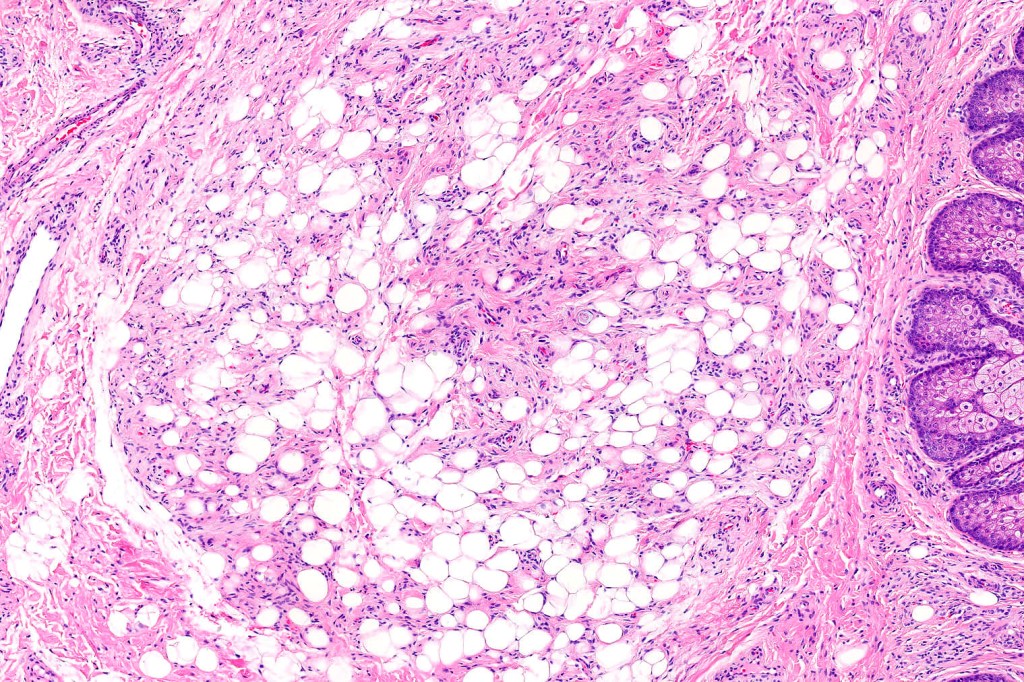

•An infundibular cyst is surrounded by laminated dermal collagen, elastic fibers, blood vessels, adipocytes & spindle cells separated from the adjacent dermis by a retraction artifact

•Exceptionally may show spindle cell lipoma-like features